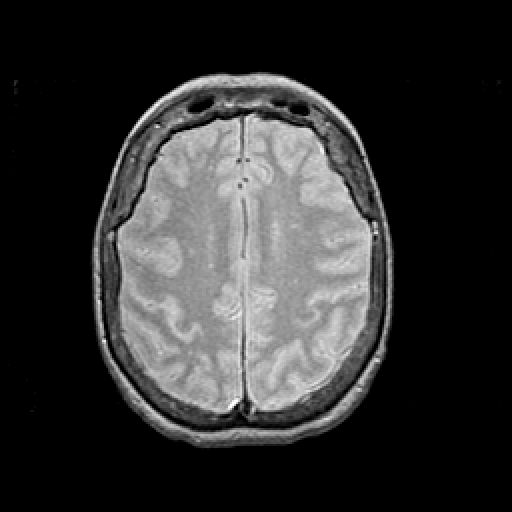

Proton density-weighted structural MR: Slice 37

Slice 37